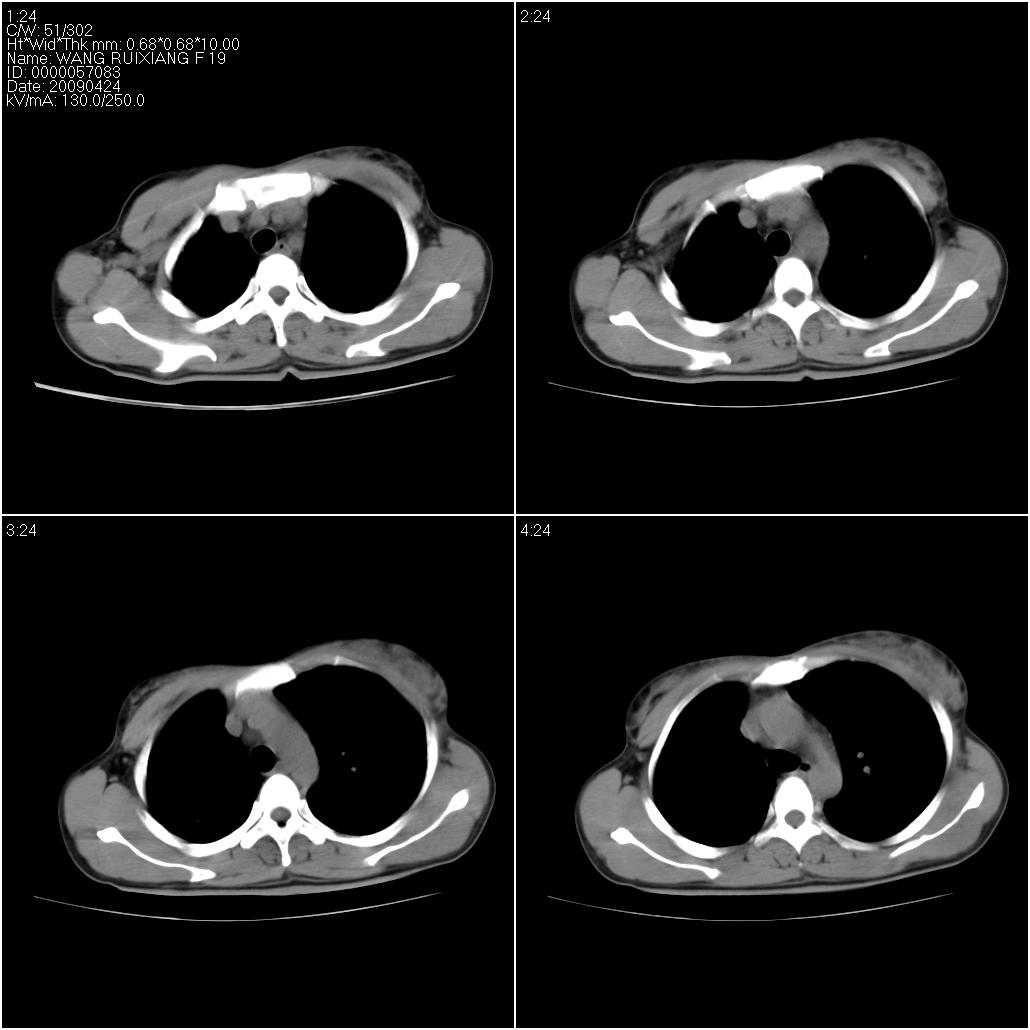

片子上的年龄为19岁,是操作错误。该患者于去年5月份曾做平片和ct扫描,和这一次的ct检查没有明显变化。当时诊断为肺结核,进行抗痨治疗至今,但没有改善。呼吸功能试验为混合型呼吸困难。除此之外,该患者没有其他方面没有的临床症状和体征

考虑肺淋巴管腺肌病,其次考虑间质性肺炎\\肺间质纤维化及韦格氏肉芽肿等

间质炎伴肺气肿,支气管扩张